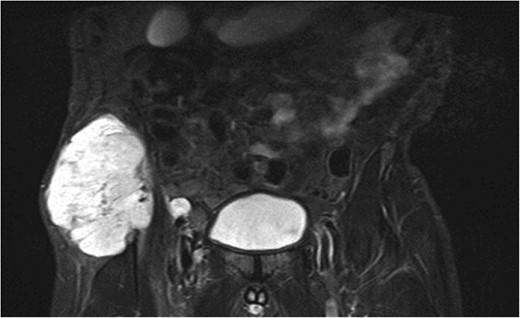

A previously fit and well 68-year-old male presented with a 6-month history of pain in the right hip. On examination this was localised to the superior area of the hip joint where a bony mass could be palpated. A pelvic radiograph was performed (Fig. 1) showing a bony exostosis on the right iliac wing. To characterise the lesion further, a pelvic Magnetic resonance imaging (MRI) scan was performed (Fig. 2). Appearances were consistent with an osteosarcoma and referral to the local sarcoma centre for histological investigation was made. Surprisingly, sampling from biopsy showed invasive well-differentiated adenocarcinoma. Staging computed tomography (CT) scanning did not reveal a primary source for the tumour but did identify thickening of the descending colon (Fig. 3) and lymphadenopathy involving the left supraclavicular, thoracic, paravertebral, retro-crurual and right inguinal regions. There was no evidence of tumour in the liver, lung or other parts of the skeleton. Subsequently, colonoscopy identified the thickened lesion as a hepatic flexure adenocarcinoma (Fig. 4). Biopsy at the time of endoscopy revealed the lesion at the hip to be a metastasis.